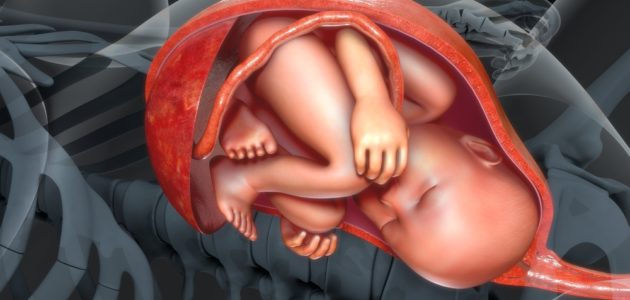

Vix publicó lo que muchas madres ya sabemos que los bebés comienzan a moverse por ahí de la semana 7 u 8 de gestación aunque los percibimos alrededor de la semana 20.

Sentir los movimientos de ese pequeño ser es una de las experiencias más significativas que experimenta al madre y toda la familia.

Conforme el bebé crece dichos movimientos se vuelven un poco más molestos y dolorosas pues el espacio se reduce y a través de la piel se producen pequeñas “montañitas” o “bultos” que pueden ser codos, rodillas o pies del bebecito. También el dorso del bebé puede sentirse completamente de un lado o de otro y ambos madre y bebé buscan acomodarse para descansar un poco y todos estos movimientos e incomodidades, son perfectamente normales.

Los movimientos del bebé son producto del ruido y sonido y después de que la mamá come, pues al procesar la glucosa, el pequeñito se activa.